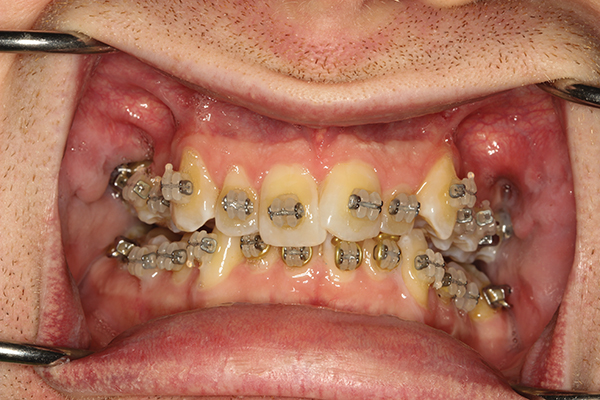

We bond them to the surface of each tooth to keep them in place throughout your treatment. If this occurs your dentist will gently clean the exposed root surface and reposition the tooth in its socket along with a splint for stability. The tooth can move away from a defect and with sufficient eruption a bony defect can be reduced or elimi-nated.

Dental Braces Orthodontics Straighten Teeth Resolve Overcrowding